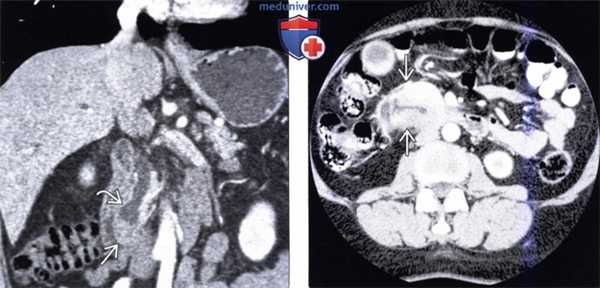

(Слева) На корональной КТ с контрастным усилением в ампуле фатерова сосочка визуализируется объемное образование округлой формы, с четкими контурами, приводящее к обструкции общего желчного протока. Рак ампулы практически всегда приводит к обструкции общего желчного протока, однако обструкция панкреатического протока возникает только в 50% случаев.

(Справа) На аксиальной КТ с контрастным усилением визуализируется инвазивная аденокарцинома ампулы фатерова сосочка, возникшая из ворсинчатой аденомы. Обратите внимание на циркулярное объемное образование большого размера (в виде «огрызка яблока») двенадцатиперстной кишки, располагающееся на границе ее второй и третьей части.